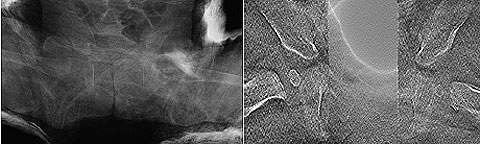

Air calibration periodically conducts one normal tomosynthesis operation for each field size to acquire the optimal calibration data for each tomosynthesis scan trajectory in order to improve the graininess. Fig. 14 shows images before and after introduction of the software. The graininess of the overall image has clearly improved. This overcomes the problems at the thinnest image reconstruction slice thickness setting, and we currently use this setting without any problems.

Grid movement control during tomosynthesis eliminates the need for the conventional moire elimination filter. It improves the horizontal resolution that was sacrificed when a moire elimination filter was used (Fig. 15).